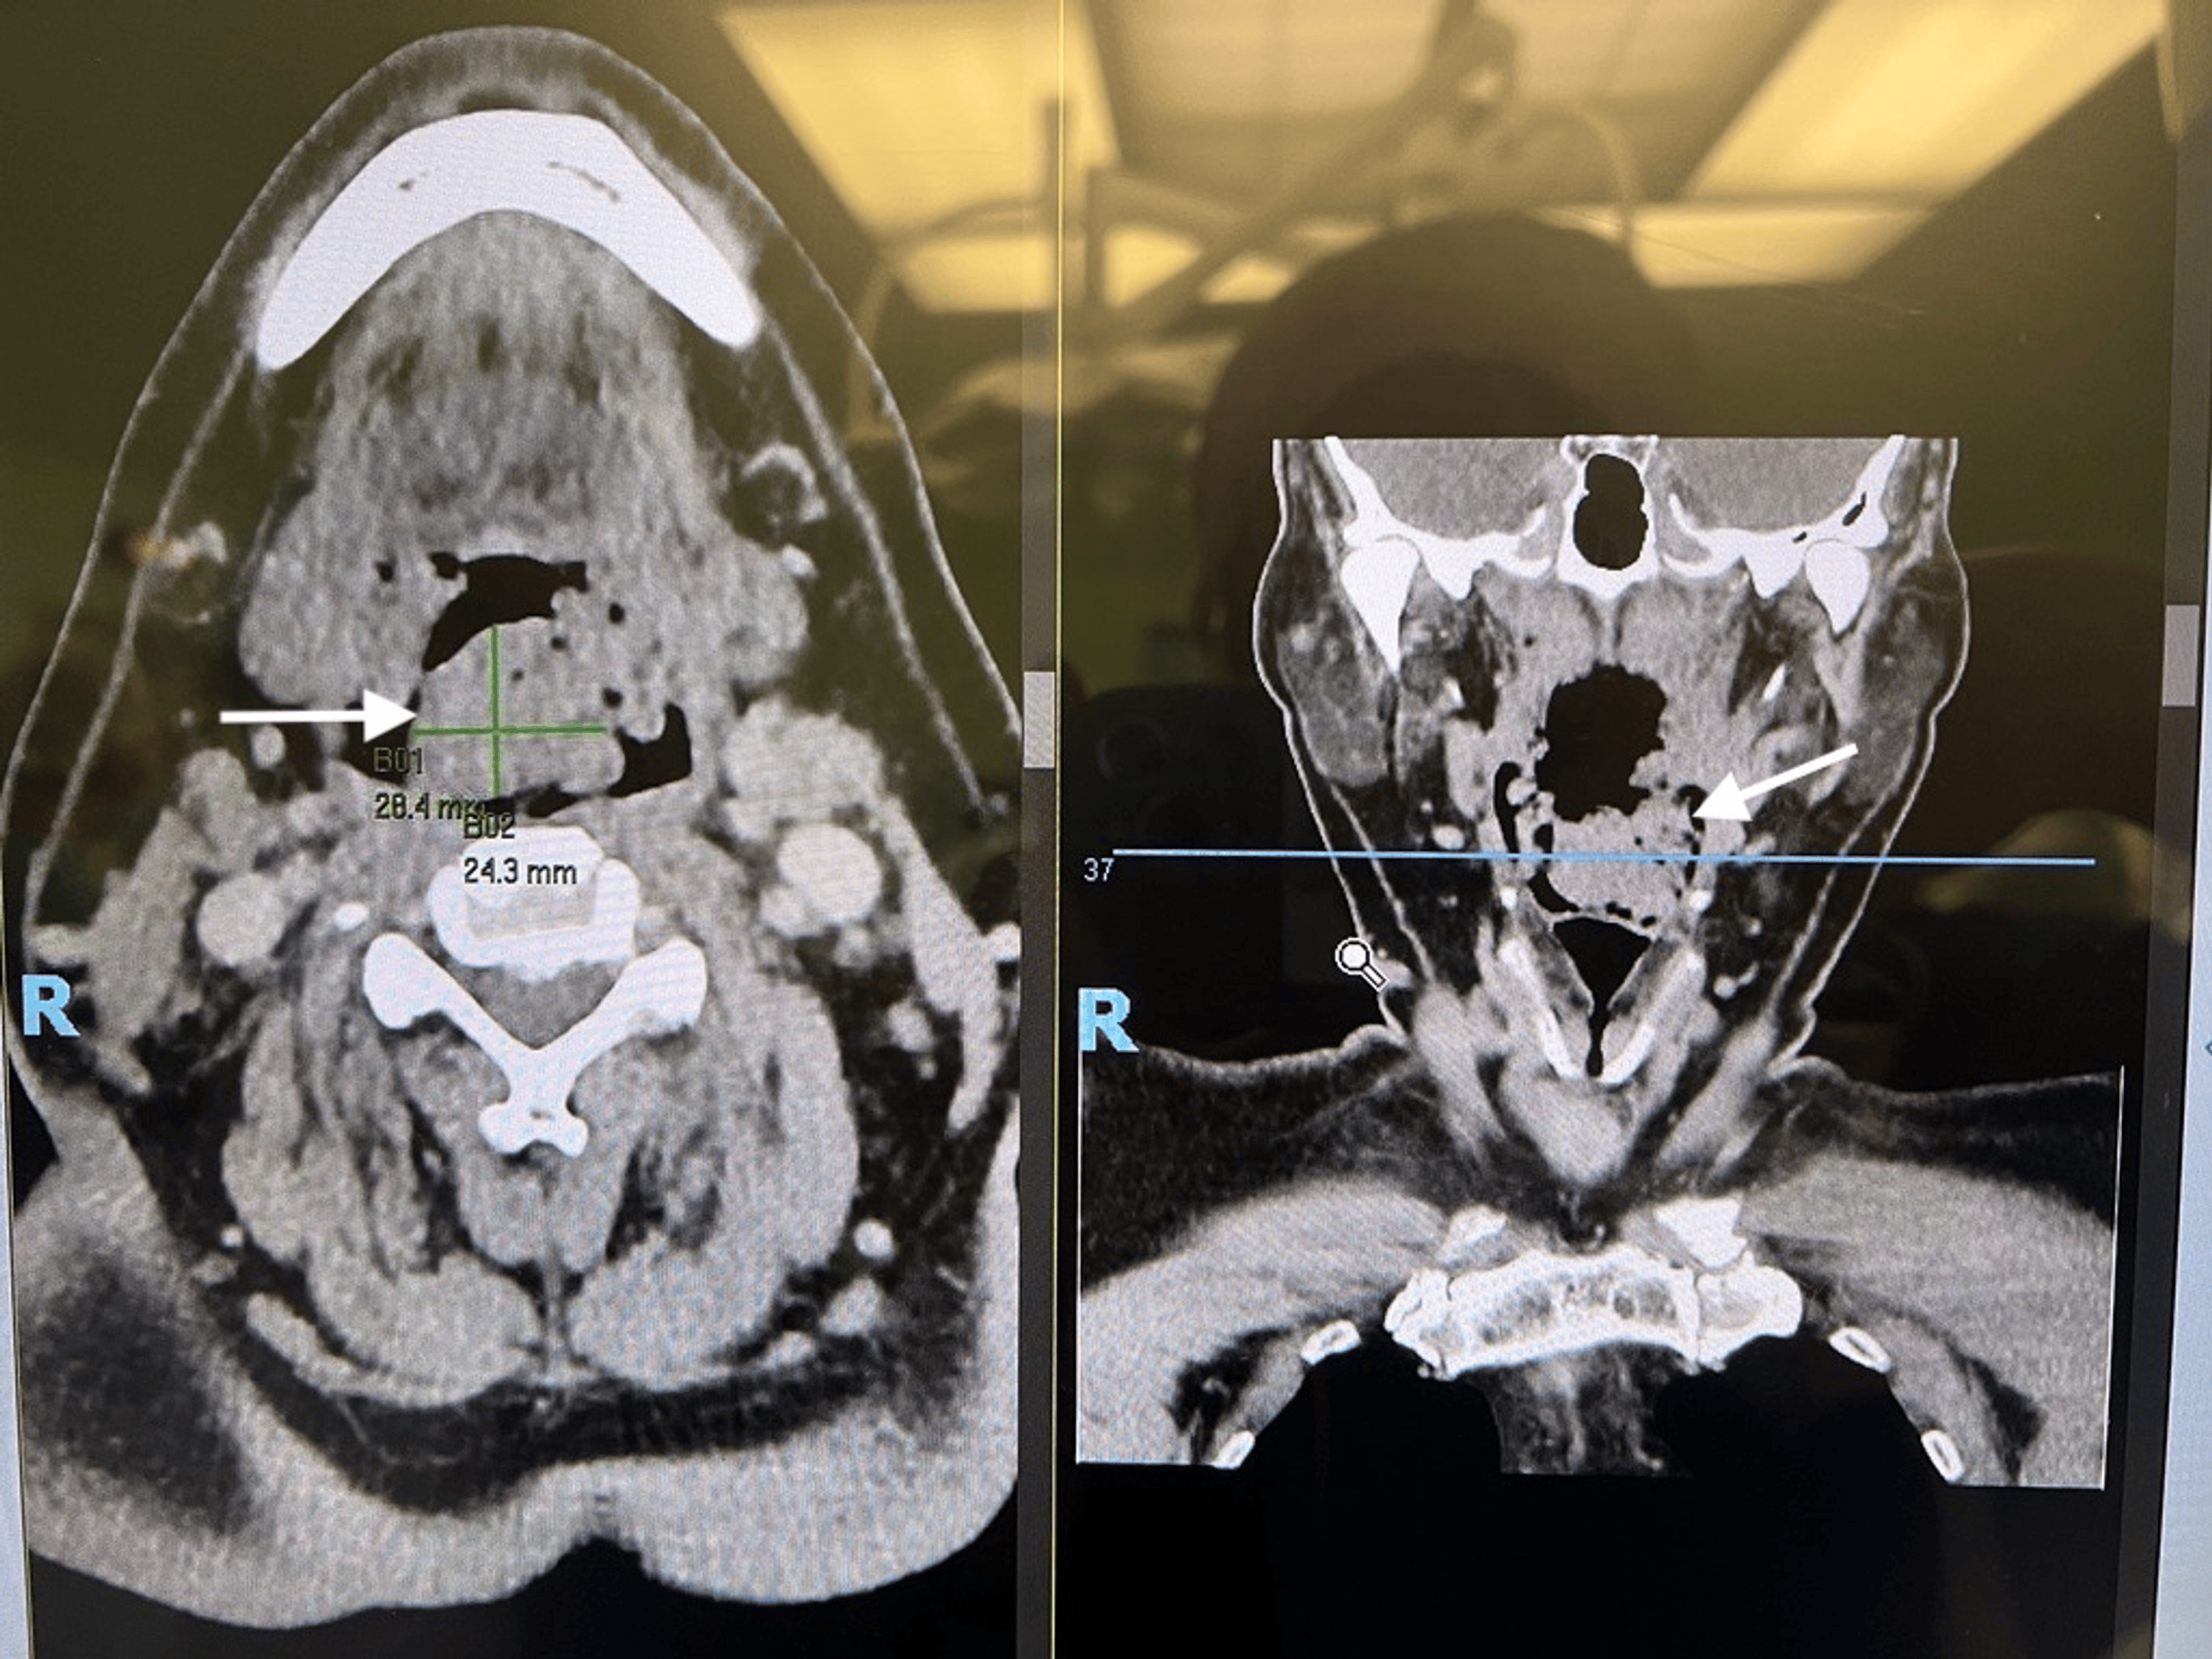

A 50-year-old man with a background of severe obstructive sleep apnea (Apnea-Hypopnea Index 70), obesity hypoventilation syndrome, obesity (BMI 38), and an epiglottic mass was electively admitted for panendoscopy, biopsy of the epiglottic mass, bilateral tonsillectomy, and lingual tonsil excision. Preoperative CT of the neck showed features suggestive of adenoidal hyperplasia with enlargement of the central nasopharyngeal soft tissues and bilateral palatine tonsils. There was also a nodular soft tissue density lesion inseparable from the epiglottis, of similar density but indeterminate nature (Figure 9). He had a Mallampati score of 3.

A 61-year-old man with a left tonsillar tumor extending up to the post-nasal space was electively admitted for biopsy, rigid esophagoscopy, and examination under anesthesia. Preoperative MRI of the neck showed a heterogeneous, enhancing, lobulated mass with lobulated margins, approximately 4.7 cm × 4.2 cm × 3.0 cm, centered at the left tonsillar fossa with local extension to the tongue base, soft palate, nasopharynx, retropharyngeal/prevertebral, and parapharyngeal spaces. It crossed the midline, resulting in near-complete effacement of the naso/oropharynx (Figure 10). He had a Mallampati score of 4.